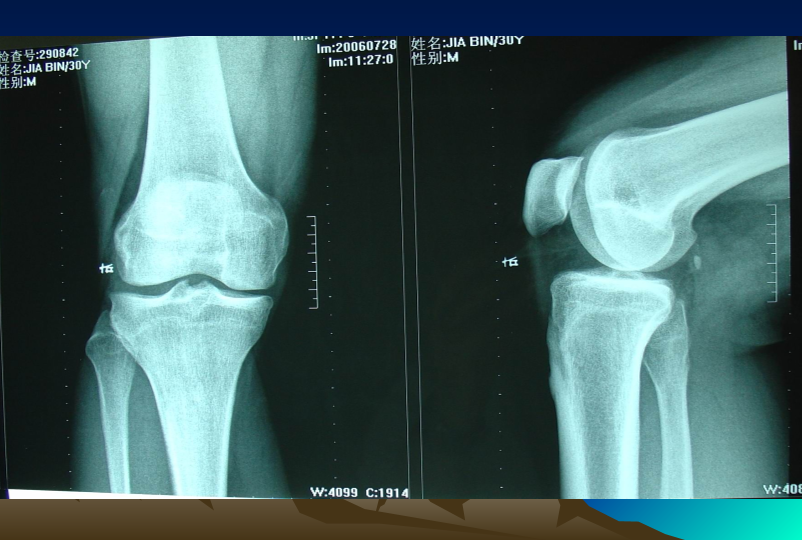

浅谈膝关节炎诊疗体会